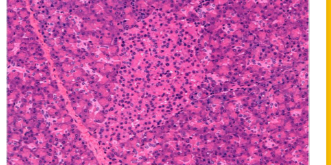

suprerenal gland / adrenal gland

adrenal gland / suprarenal

adrenal gland